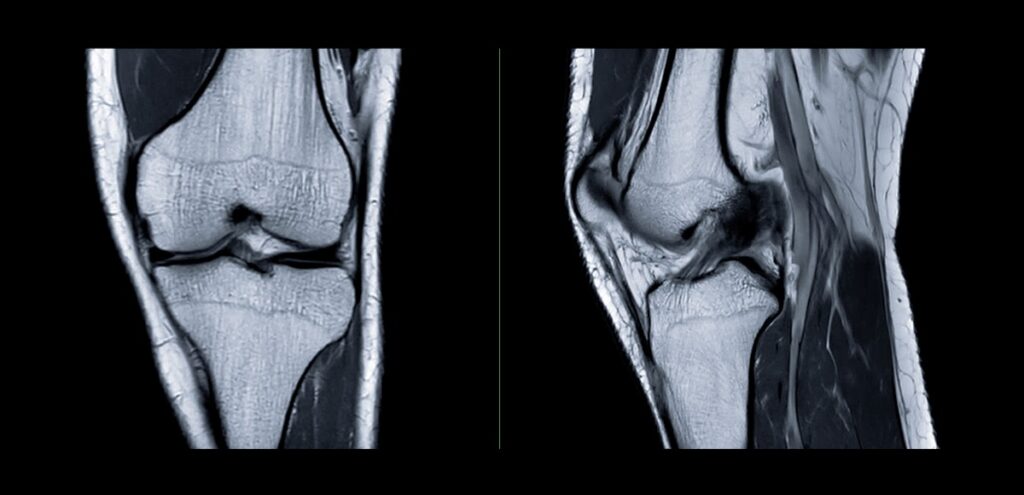

Risonanza magnetica nucleare (RMN) Dischi intervertebrali, midollo spinale, radici nervose, legamenti, tessuti molli Ernie discali, stenosi del canale spinale, mielopatie, lesioni midollari, patologie infiammatorie o degenerative Esame più completo, non utilizza radiazioni ionizzanti, controindicata con alcuni dispositivi metallici impiantati